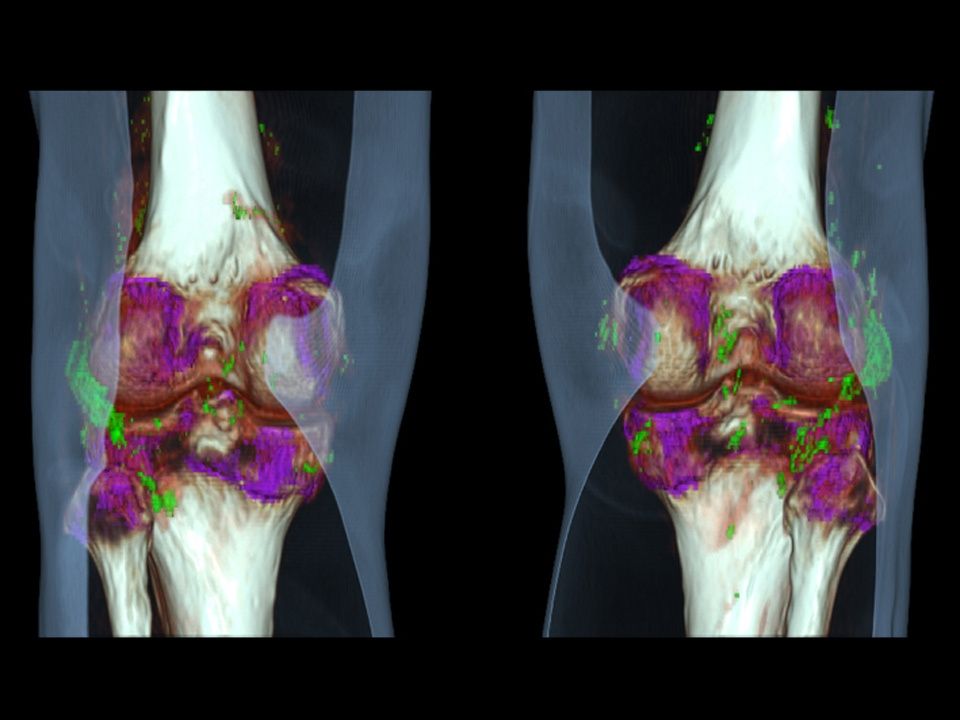

CT DE Gout

Accurate and non-invasive diagnosis of gout.